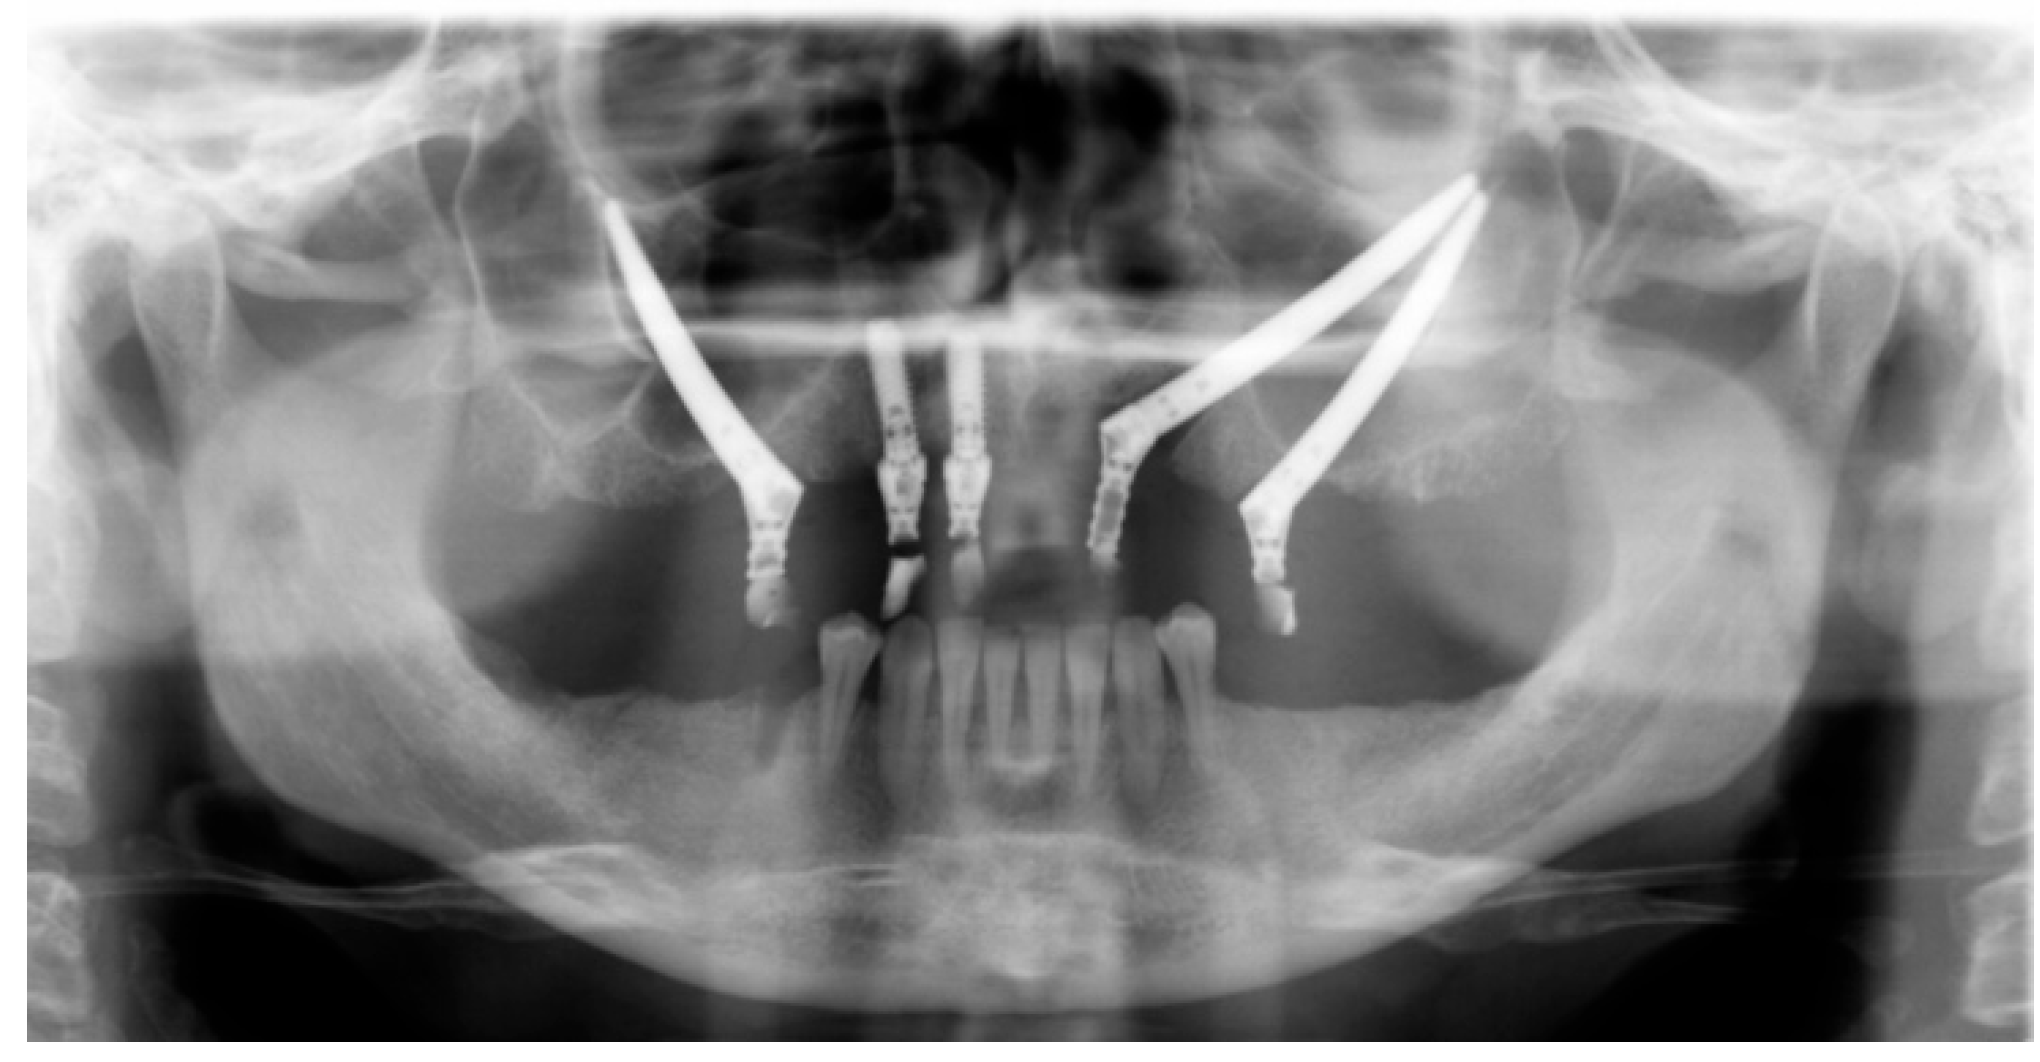

At the intraoral inspection, after removing the overdenture, no signs of infection were revealed. On the orbito-zygomatic region a skin fistula was present (Figure 2). The orthopantomography showed on the right side one zygomatic implant along with two conventional fixtures in the premaxilla area. A CBCT was performed. On the left side 2 ZIs were inserted with emergence, respectively, in the canine and in the premolar area. The etched apical portions appeared to be almost in contact, with 1 mm distance or less between them. (Figure 3 and Figure 4).

Figure 3.

Panoramic radiograph, showing two ZIs on the left side with their apex in close contact without adequate inter-implant distance.